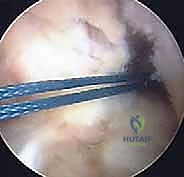

شكل 3: تجهيز الطعم الوتري (Graft Preparation) بعناية فائقة. يتم اختيار الطعم المناسب وتجهيزه ليكون بالقوة والسمك المناسبين لركبة الطفل.

شكل 5: رؤية بالمنظار الجراحي بتقنية 4K عالية الدقة لمفصل الركبة من الداخل، مما يتيح للأستاذ الدكتور محمد هطيف رؤية أوضح للتشريح الدقيق وإجراء الجراحة بأقل قدر من التدخل الغازي.

شكل 6: تمرير الطعم الوتري الجديد داخل الركبة بمهارة عالية. يتم سحب الطعم عبر الأنفاق العظمية أو حولها ليتخذ الوضع التشريحي الدقيق للرباط الصليبي الأصلي.